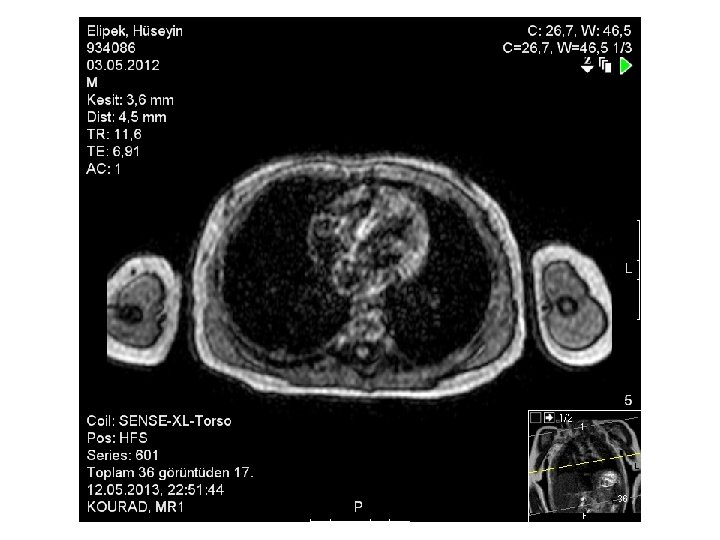

12/05/2013 Tarihli Toraks MR • 24/04/2013 tarihli MR incelemede sağ akciğer alt lobda tanımlanan abse lezyon günümüz MR incelemesinde gerilemiş olup bu lokalizasyonda sekel değişiklikler mevcuttur.

09/04/2013 Tarihli Toraks MR • Akciğer parankim alanlarının değerlendirilmesinde; aktif infiltratif görünüm ve nodüler lezyon saptanmadı. • Sağ akciğer alt lobda 9 x 14 mm boyutlu abse ile uyumlu içerisinde hava bulunan kalın duvarlı ve duvarı kontrast tutan kitle lezyon izlenmektedir. • Hastanın 26/03/2013 tarihli toraks BT incelemesine göre boyutları küçülmüştür. • Ayrıca sağdaki plevral efüzyon gerilemiştir. • Sağ akciğer alt lob posteriorda hafif konsolide görünüm izlenmekte olup, 26/03/2013 tarihli incelemeye göre gerilemiştir.

24/04/2013 Tarihli Toraks MR • 09. 04. 2013 tarihli MR incelemede sağ akciğer alt lobda izlenen kalın duvarlı abse ile uyumlu lezyon günümüz MR incelemesinde belirgin derecede küçülmüş olup çapı 1 cm ölçüldü. • Sağda bu alan komşuluğunda plevrada fokal kalınlaşma ve minimal plevral efüzyon izlenmektedir. • Sağ akciğer alt lob posteriorda hafif konsolide görünüm izlenmekte olup, 26/03/2013 tarihli incelemeye göre gerilemiştir.